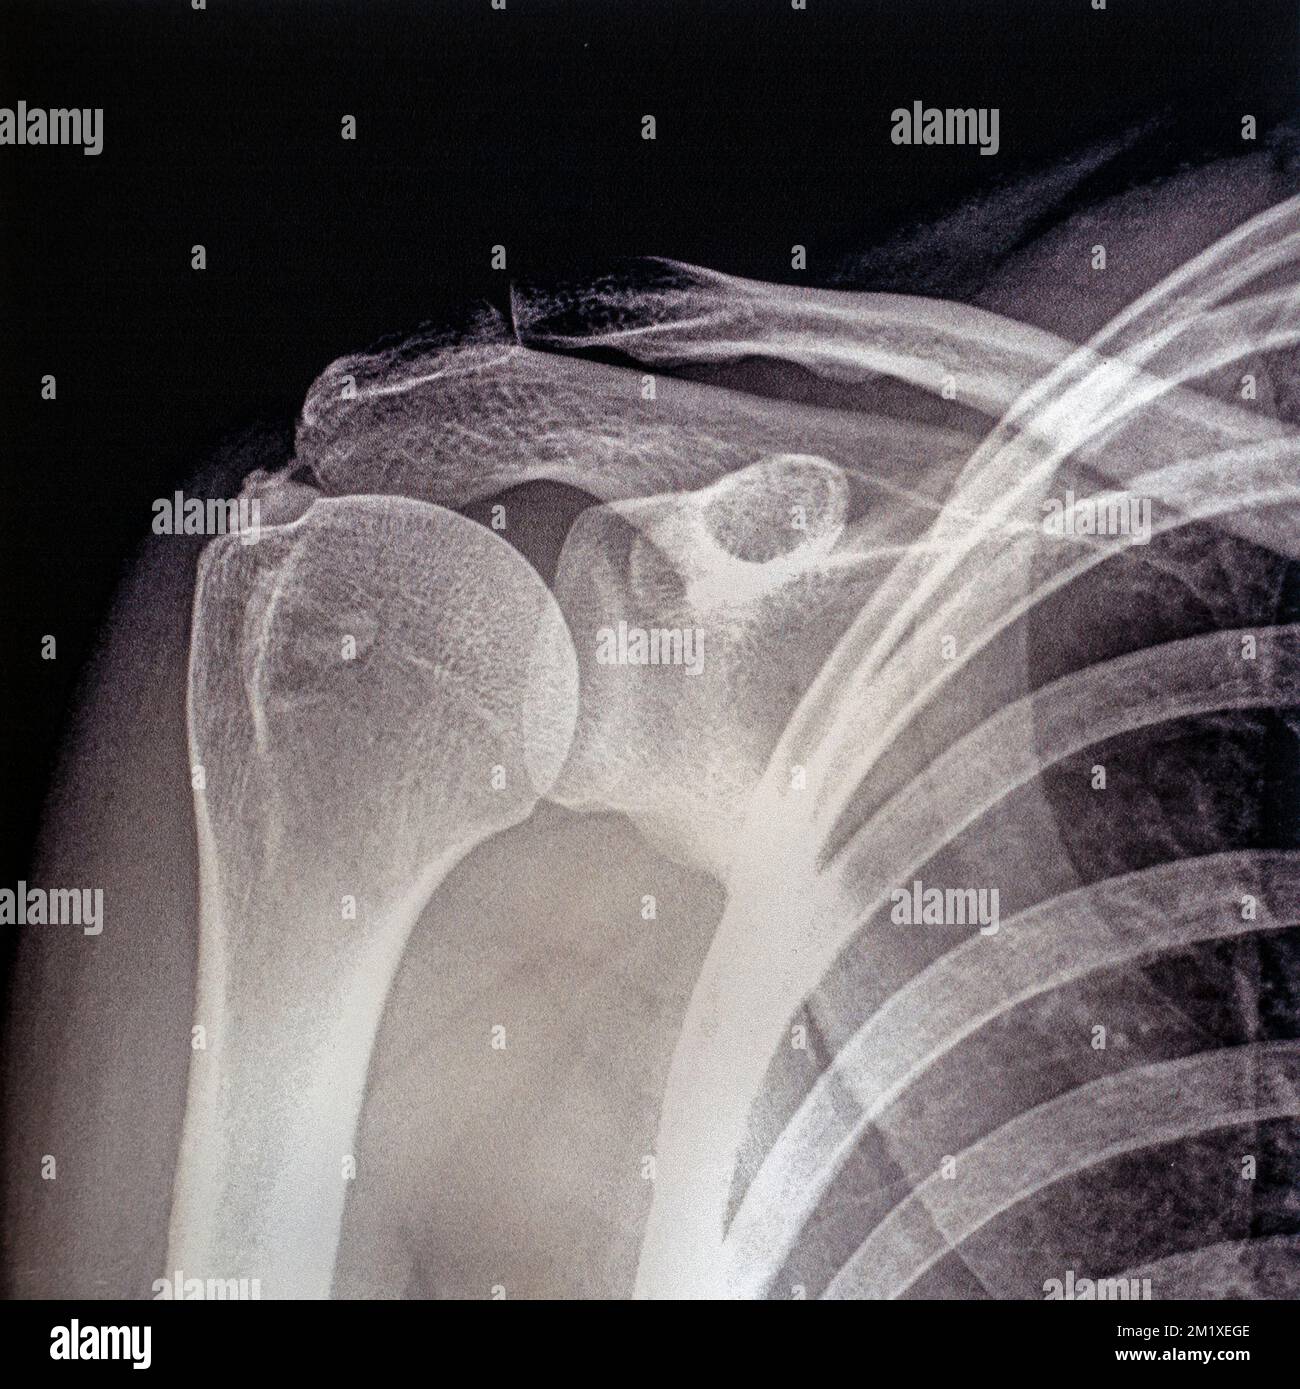

X Ray Shoulder Internal Rotation . Diagram of internal rotation of the shoulder. The stronger the magnet, the higher the intrinsic. The red arrow points to the lesser tubercle of the humerus in profile. Ap in internal rotation for visualization of the lesser tuberosity. The red shaded oval is the overlap between the humeral head and. The humeral head will lie posterior to the glenoid fossa. Mri is best for evaluating soft tissue structures and evaluating bone contusions or trabelcular microfractures. Radiographic examination of shoulder in ap view with internal rotation. The glenohumeral joint will be widened and the humeral head will take on a classic “light bulb” appearance due to forced internal rotation of the humerus. The american college of radiology recommends at least 3 views for acute traumatic shoulder pain [5]: Radiographic positioning included in this video are the anteroposterior (ap) internal rotation and. This projection demonstrate fracture and dislocation of the proximal humerus and shoulder girdle. The shoulder series is fundamentally composed of two orthogonal views of the glenohumeral joint including the entire.

X Ray Shoulder Internal Rotation The red shaded oval is the overlap between the humeral head and. The shoulder series is fundamentally composed of two orthogonal views of the glenohumeral joint including the entire. Mri is best for evaluating soft tissue structures and evaluating bone contusions or trabelcular microfractures. Diagram of internal rotation of the shoulder. The stronger the magnet, the higher the intrinsic. The american college of radiology recommends at least 3 views for acute traumatic shoulder pain [5]: Radiographic examination of shoulder in ap view with internal rotation. The red arrow points to the lesser tubercle of the humerus in profile. Radiographic positioning included in this video are the anteroposterior (ap) internal rotation and. The red shaded oval is the overlap between the humeral head and. The humeral head will lie posterior to the glenoid fossa. Ap in internal rotation for visualization of the lesser tuberosity. The glenohumeral joint will be widened and the humeral head will take on a classic “light bulb” appearance due to forced internal rotation of the humerus. This projection demonstrate fracture and dislocation of the proximal humerus and shoulder girdle.

Right shoulder internal rotation and external rotation radiographs X Ray Shoulder Internal Rotation Diagram of internal rotation of the shoulder. The glenohumeral joint will be widened and the humeral head will take on a classic “light bulb” appearance due to forced internal rotation of the humerus. The red shaded oval is the overlap between the humeral head and. Mri is best for evaluating soft tissue structures and evaluating bone contusions or trabelcular microfractures.. X Ray Shoulder Internal Rotation.

Coloured Xrays of the right shoulder of a 36 year old patient that has X Ray Shoulder Internal Rotation The shoulder series is fundamentally composed of two orthogonal views of the glenohumeral joint including the entire. The glenohumeral joint will be widened and the humeral head will take on a classic “light bulb” appearance due to forced internal rotation of the humerus. Mri is best for evaluating soft tissue structures and evaluating bone contusions or trabelcular microfractures. Diagram of. X Ray Shoulder Internal Rotation.